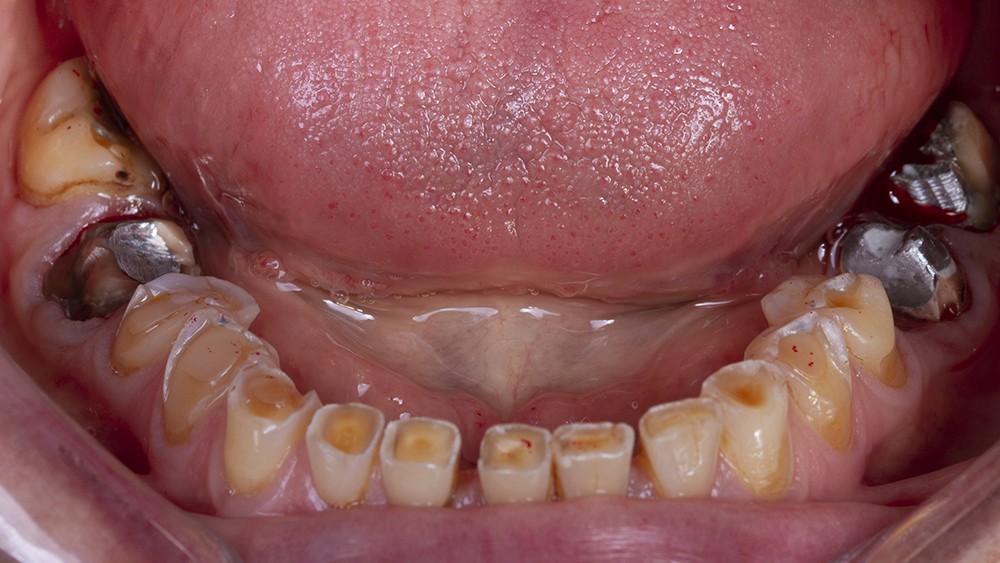

Le calage postérieur obtenu assure l’augmentation de la DVO et entraîne très souvent une béance antérieure avec une perte du guidage antérieur (fig. 8). Le traitement du groupe incisivo-canin est alors nécessaire.

La forme clinique des restaurations d’usage dépend de l’étendue de la perte tissulaire. Lorsque cette dernière est modérée, la réalisation de facettes vestibulaires permet le rallongement des bords libres usés dans le prolongement du rehaussement postérieur.

Dans les cas d’usure des faces palatines, la restauration du guide antérieur suppose une reconstruction grâce à la technique 3-step ou par des facettes en céramique dites à 360°. Dans cette dernière option, les faces palatines usées ne nécessitent qu’un congé fixant la limite prothétique, maximisant ainsi la préservation tissulaire et optimisant le collage à venir.